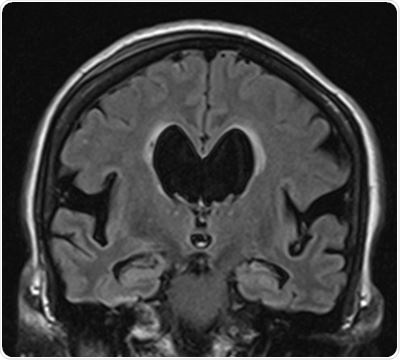

In iNPH, the circulation of cerebrospinal fluid (CSF) is disturbed for an unknown reason, leading to a slightly elevated brain pressure and dilation of the brain ventricles. Symptoms of NPH include gait deviations, impaired short-term memory and urinary incontinence. Patients with iNPH often have changes in brain that are related to Alzheimer’s disease.

During the follow-up, the researchers found that up to one in five patients with NPH were later diagnosed with Alzheimer’s disease. At the end of the follow-up, patients with NPH were more frequently diagnosed with Alzheimer’s disease than the general population. The researchers were able to predict the development of Alzheimer’s disease, with moderate accuracy, by using patient-specific DSI. The data used in DSI included the patient’s pre-surgery symptom profile, brain tissue samples and brain MRI images.